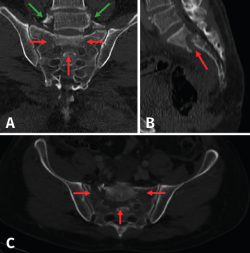

La visualización tanto en radiografía simple como en la TC de fracturas en las apófisis transversas de L5 nos ha de hacer sospechar fractura sacra(9)(Figura 2). Estos procesos se hallan conectados con el hueso iliaco por medio de los potentes ligamentos iliolumbares. En presencia de fuerzas axiales de alta energía, las apófisis transversas suelen fracturarse indicando con una alta probabilidad fracturas sacras.

Figura 2. A: Reconstrucciones coronales ; B: sagitales; y C: axiales de sacro. En la imagen coronal (A) podemos apreciar la fractura de apófisis transversas de L5 que indican de manera indirecta una posible fractura sacra. Igualmente, en el plano coronal podemos apreciar dos trazos de fractura que discurren por los forámenes de S1 (Denis II) asociadas a una fractura transversa que dan como resultado una fractura en U de sacro con la consiguiente disociación espinopélvica como resultado. En el plano sagital (B) podemos apreciar el trazo de fractura a nivel de S1 y su listesis anterior sobre S2, resultando una fractura de tipo 3 de Roy-Camille. En el plano axial (C) vemos la completa desvinculación del fragmento proximal sacro del resto de la pelvis.

Por tanto, basándonos en las clasificaciones antes descritas, caracterizamos nuestra fractura como una fractura sacra en U, Denis III, Roy-Camille de tipo 3 asociada a lesión del anillo pélvico anterior en forma de diástasis de la sínfisis púbica (Figura 2).